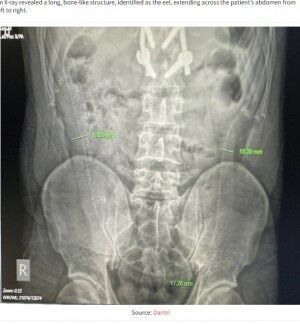

腹痛の原因について聞かれた男性は「正午頃、肛門から大きなウナギを挿入した」と答えた。医師は早速、複数の検査を行い、レントゲン検査でウナギと分かるような長い骨が男性の腹部を横切るように左から右へ伸びていることを確認した。